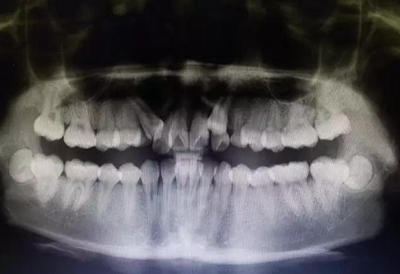

全景片